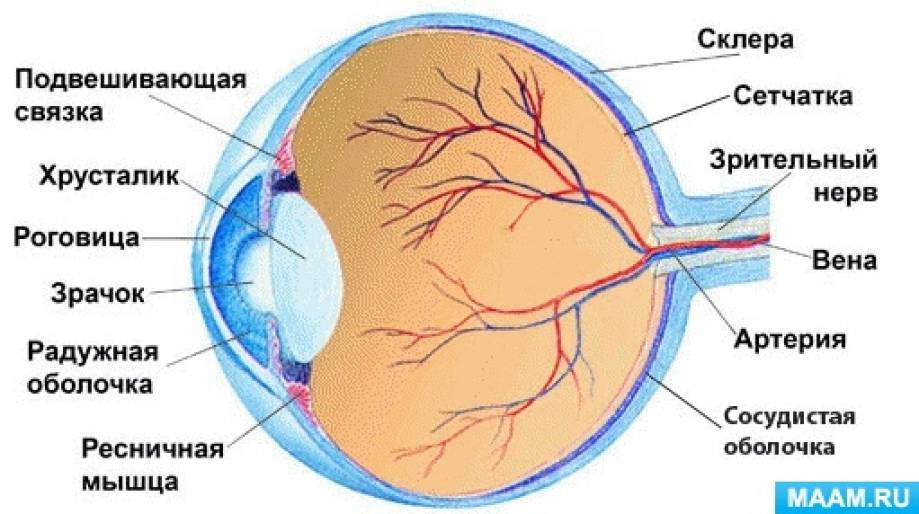

КТ-графики и изображение строения глаза